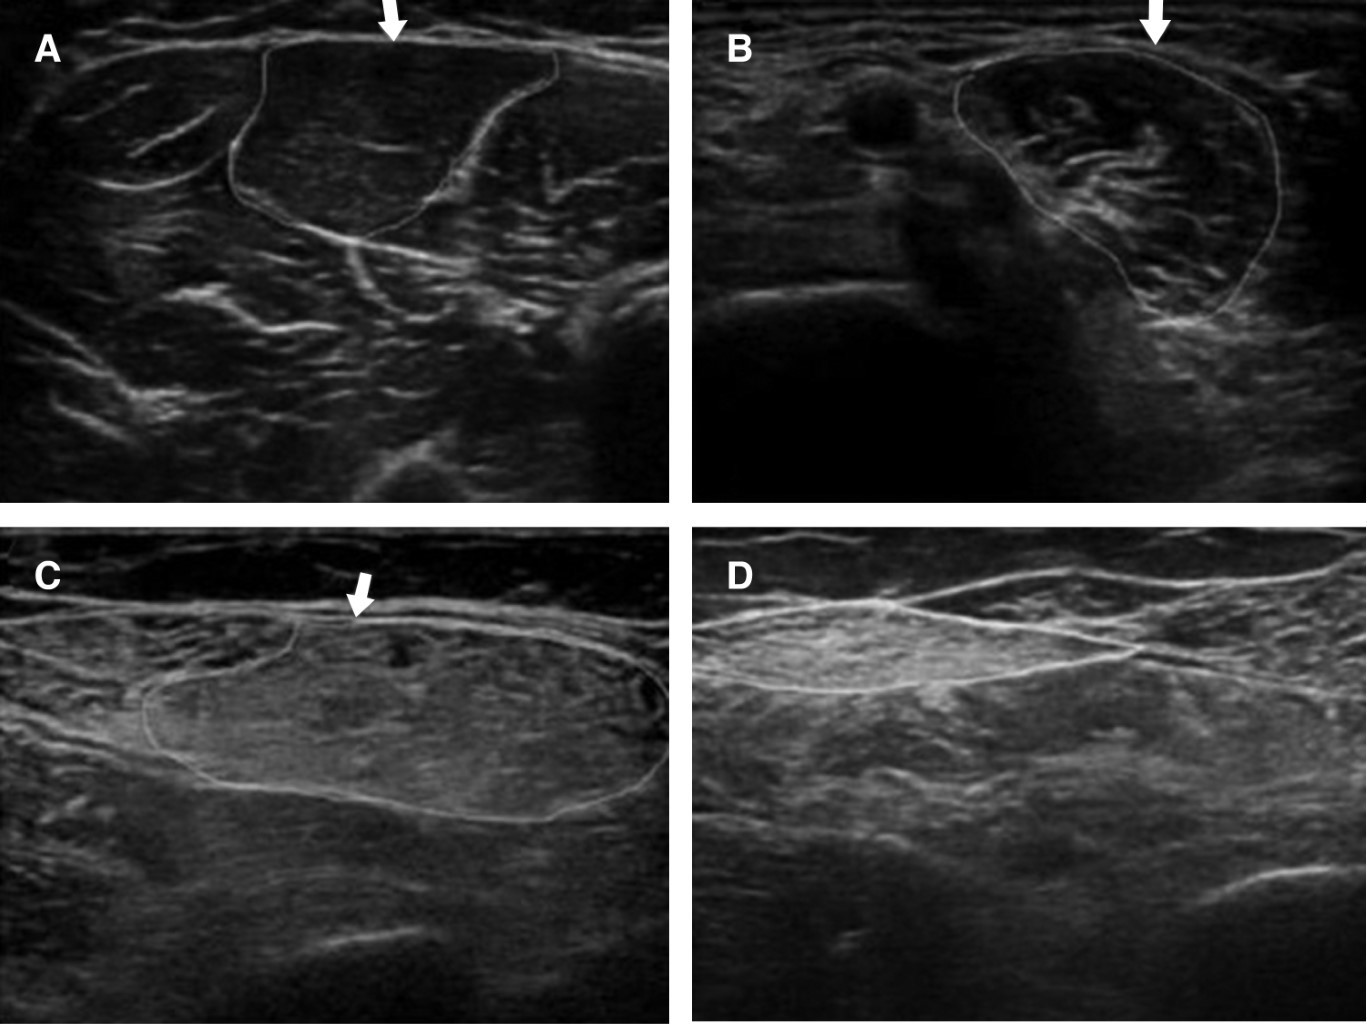

Las escalas de Heckmatt normal y modificada son las técnicas ultrasonográficas que, de acuerdo a estadificación de cuatro grados, permiten evaluar el músculo y determinar el grado de sarcopenia en un paciente. Grado 1 normal: ecogenicidad normal en más del 90% del músculo que es distinto del eco óseo; grado 2: aumento de la intensidad del eco muscular con eco óseo distinto, aumento de la ecogenicidad muscular en 10-50% del tejido, pero con eco óseo distinto y áreas de eco muscular normal; grado 3: marcado aumento de la intensidad del eco muscular con un eco óseo reducido, marcado aumento de la ecogenicidad muscular entre 50 y 90% del tejido con una distinción reducida del eco óseo del músculo; grado 4: eco muscular muy fuerte y pérdida completa del eco óseo, ecogenicidad muscular muy fuerte con pérdida casi completa del eco óseo distinto del músculo en más de 90% del tejido.25

La técnica se describe con el paciente en posición supina con las rodillas extendidas y los dedos de los pies apuntando hacia el techo. Con una cinta métrica no elástica, trazar una línea imaginaria en la parte anterior del muslo desde la espina ilíaca anteroinferior (AIIS) hasta el punto medio del borde proximal de la rótula y marcar la mitad y un tercer punto entre estas dos referencias que fácilmente nos da acceso al recto femoral y vasto interno. Se requiere un equipo de ecografía con modo bidimencional, así como un transductor lineal o sonda (frecuencia: 7-13 MHz) que nos permitan obtener imágenes de alta resolución de las estructuras superficiales. Una frecuencia más alta genera una resolución más alta a expensas de una profundidad de imagen reducida. Para obtener una imagen transversal, el transductor debe ser orientado transversalmente al eje longitudinal (el imaginario de línea marcada antes) del muslo formando un ángulo de 90o en relación con la superficie de la piel (Anexo 1) .26

En cuanto a la técnica de medición de sarcopenia por ultrasonido, se utilizó con un equipo de ultrasonido marca philips No ID Ultrasonido, Affiniti 500 G, serie USN 19D 0683, con el paciente en posición supina, con las rodillas extendidas y los dedos de los pies apuntando hacia el techo. Con una cinta métrica, se trazó una línea imaginaria en la parte anterior del muslo desde el ángulo interno del isquion hasta el punto medio del borde proximal de la rótula y se marcó la mitad y un tercer punto entre estas dos referencias, que fácilmente brinda acceso al recto femoral y vasto interno (Anexo 1) . Con modo bidimensional, con un transductor lineal (frecuencia: 7-13 MHz) L15-7io, que permiten obtener imágenes de alta resolución de las estructuras superficiales, se obtuvo una imagen transversal; el transductor se orientó transversalmente al eje longitudinal (el imaginario de línea marcada antes) del muslo formando un ángulo de 90o en relación con la superficie de la piel. Se obtuvo la valoración de acuerdo a la escala de Heckmatt para la estimación nutricional, asignando uno de los cuatro grados mencionados en el Anexo 1.

Al momento del ingreso en UCI, de los 70 pacientes incluidos, 10 (14.28%) presentaban sarcopenia (valorada por ultrasonido del músculo recto femoral en la porción anteroposterior); evolutivamente, 14 pacientes cumplieron con el diagnóstico de sarcopenia. Sin embargo, en el análisis por rango intercuartílico, de las variables cuantitativas de la medición ultrasonográfica del músculo recto femoral en la porción anteroposterior (USG musc RF-AP) y laterolateral (USG musc RF-LL) sí presentaron diferencia (Figura 1).